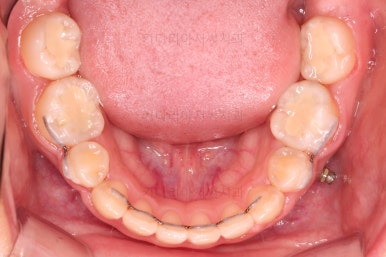

딱 한 개의 치아만 발치되어 있었는데 추가적으로 균형을 맞추기 위해 반대편 치아도 발치를 하고 아랫니 유치도 뽑았어요.

유치 어금니는 크기가 매우 크기 때문에 빈자리 만큼 모두 앞니를 뒤로 당기면 입이 너무 들어가게 된답니다.

따라서 얼마나 효과적인 방법으로 적절한 양만큼 어금니를 앞으로 당겨올 것인가가 이번 치료의 핵심이었어요.

미니스크류가 등장했네요.

아랫니는 아무 생각 없이 당기기 해주면 앞니가 너무 들어가 입이 합죽해질 수 있으니 앞니가 들어가는 양을 조절하기 위해서 미니스크류를 사용해주어요.

적절한 시기부터는 어금니만 100% 앞으로 당겨와야 했기 때문이죠.

이원교정을 하신지 총 30개월 만에 남아있던 유치 자리가 잘 다물어졌고요.

이 뽑은 자리도 잘 메워졌고, 앞니도 가지런해졌어요.

위아래 치아 갯수도 동일하게 교합도 잘 맞췄고요.

예상보다 빠른 기간 안에 매우 만족스러운 치료였어요.